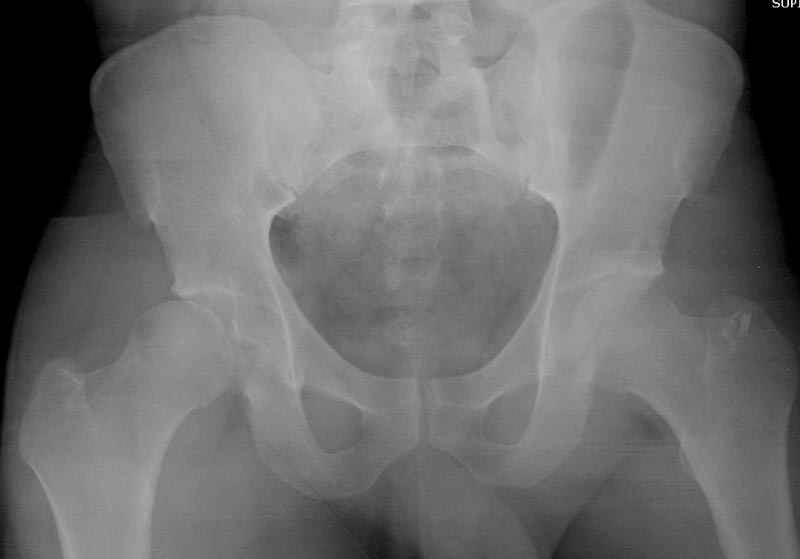

5:24 Рентгенограмма таза, вызывают врача ортопеда (снимок N1), его диагноз: закрытый переломо-вывих правого тазабедренного сустава, получает добро на закрытую репозицию в приемном отделении

5:38 Дважды неудачная попытка закрытой репозиции в приемном отделении

N 2